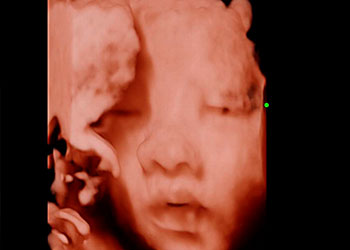

Ejemplos de ecografías del embarazo